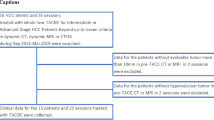

To evaluate the relationships among VLs, additional GS embolization, and local response, the 338 nodules were retrospectively divided into three groups according to the onset of VLs and the need for additional GS embolization to deal with non-shrinking VLs: lesions without a VL (non-VL group, n = 250); lesions with a VL but without an additional GS embolization [VL–GS (−) group, n = 58] (Fig. 1); and lesions with both VL and additional GS embolization following DEB injection [VL–GS (+) group, n = 30] (Fig. 2).

A lesion with a vascular lake (VL) that was additionally injected with gelatin sponge particles (GS) in the VL–GS (+) group. The patient was an 84-year-old male with a solitary 3.5-cm hepatocellular carcinoma (HCC) in the right hepatic lobe. a Selective angiography of the posterior superior subsegmental branch of the right hepatic artery showed a tumor blush. Chemoembolization was performed at this point. b After chemoembolization using 7 mg of drug-eluting beads (DEBs), selective angiography showed the onset of VL (arrow) and residual tumor blush. c After additional chemoembolization using 8 mg of DEBs, the majority of the tumor blush disappeared, and the size of the VL evidently increased. d Additional embolization using GS was performed until the VL disappeared completely